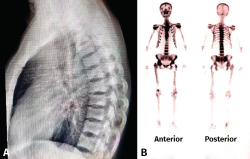

Gammagrafía ósea(27)

Es un método de medicina nuclear para obtener imágenes del esqueleto que representan la expresión del metabolismo óseo. Constituye una técnica diagnóstica sensible, con capacidad para proporcionar de una forma precoz, aunque poco específica, información sobre múltiples alteraciones esqueléticas de origen metabólico, traumático, infeccioso o tumoral.

Tiene las ventajas de no ser invasiva, con una tasa de irradiación muy baja en comparación con otras y con un coste inferior a la TAC y la RM, aunque bastante superior a la radiología simple. El tecnecio-99m es el isótopo que se usa más frecuentemente, unido a un difosfonato que tiende a fijarse en el hueso al ser absorbido en la superficie del cristal de hidroxiapatita.

Resulta particularmente adecuada cuando las radiografías no son capaces de detectar aún el aumento de actividad ósea, es decir, en etapas muy precoces. El problema radica en su poca especificidad ante una hipercaptación, que puede significar cualquier proceso inflamatorio como infección, tumor, fractura, etc.

Figura 14. Gammagrafía ósea. Reproducido de Ospina Caicedo et al.(28).

En pacientes con dolor lumbar, estaría indicada su realización ante la sospecha clínica de una patología específica grave (neoplasia, infección vertebral, fractura reciente), derivada de la historia clínica, el examen físico o la analítica convencional, y cuando la radiología simple es normal o poco evidente ante clínicas prolongadas sin diagnóstico. Estos estudios son de escasa utilidad en la patología mecánica, con la excepción de la espondilosis ístmica, no detectable en la radiología simple (Figura 14)(28).